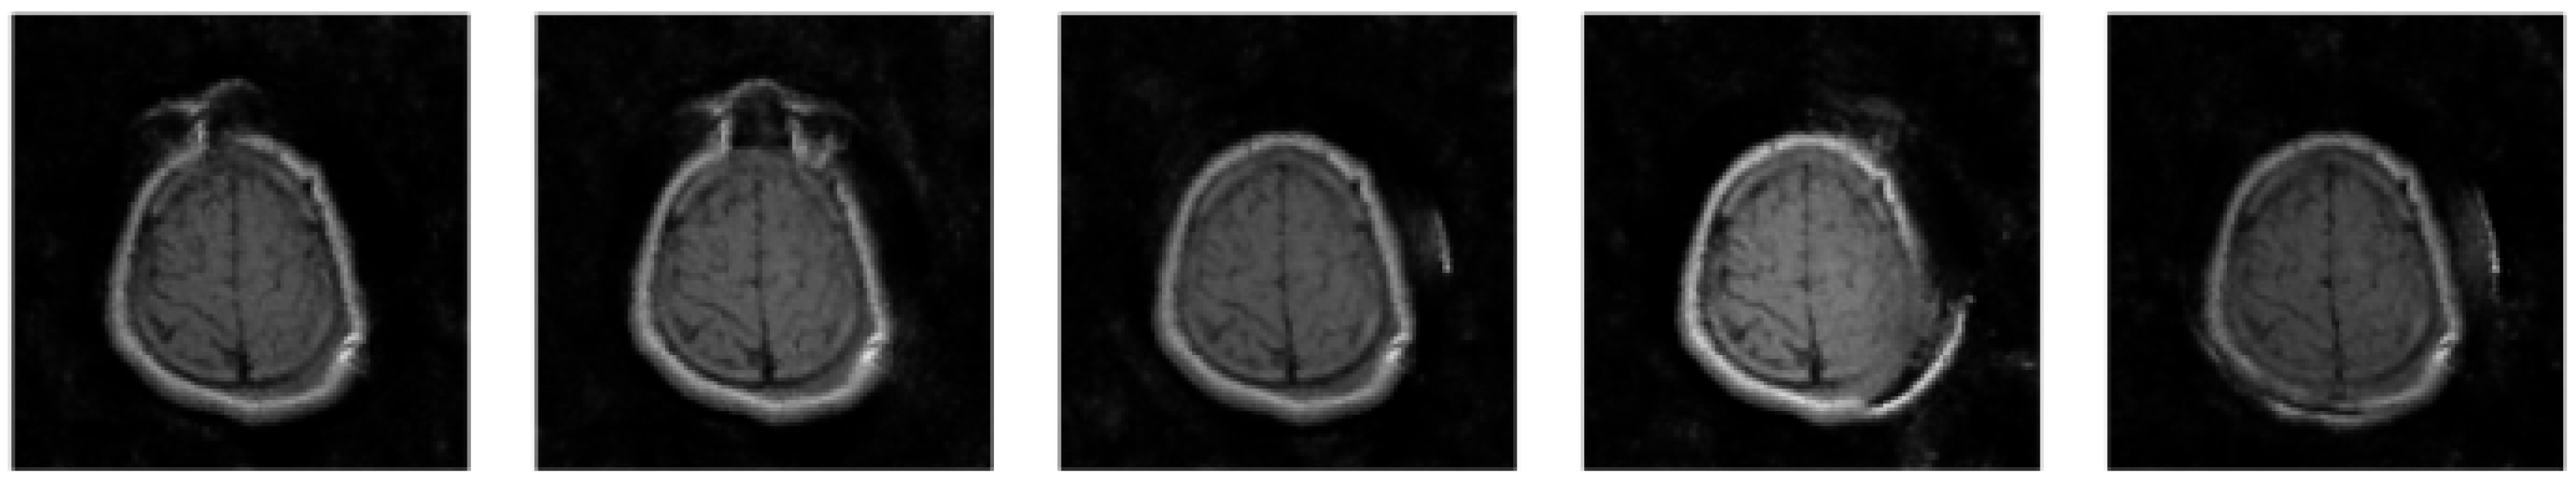

3.2. Data Augmentation and Generative Adversarial Networks